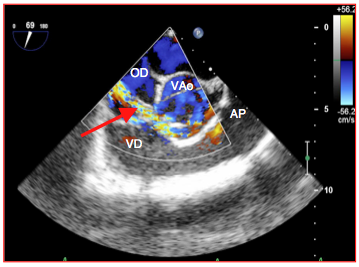

La fistule est une communication anormale entre deux cavités résultant de la rupture d’un abcès ou d’un pseudo-anévrysme. Elle relie le plus souvent un sinus de Valsalva avec l’OD ou l’OG (Vidéos et Figure 26.165).

Figure 26.165 : Fistule endocarditique entre le sinus de Valsalva droit et l'OD; le jet tourbillonnaire (flèche rouge) passe de l'aorte à l'oreillette droite juste en amont du feuillet tricuspidien et réalise un important shunt gauche – droit avec surcharge des cavités droites.